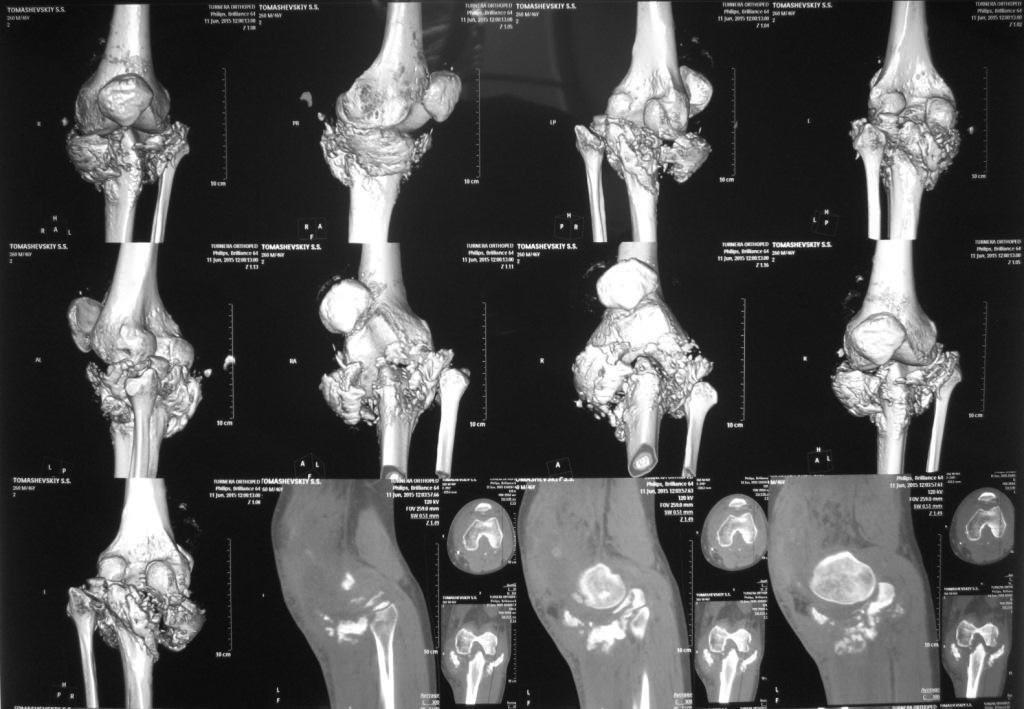

[Ortho] КТ сложного перелома TIBIA

Пациент выполнил КТ коленного сустава. У кого как-то изменилось мнение

про тактику, пожалуйста, напишите. Спасибо

Имя     : IMG_7611.JPG

Размер  : 130825 байтов